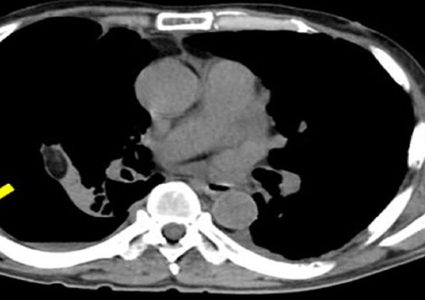

تضخم فقاعة هوائية تحت الجلد يسبب آلاماً شديدة

تكونت تحت جلد أحد مواطني اليابان المصاب بسرطان الرئة، فقاعة هوائية قطرها ثمانية سنتمترات وسببت له آلاما شديدة. ولكن خلال بضعة أيام كان يعاني من …